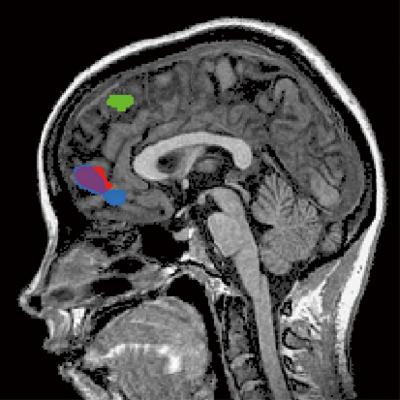

The authors found that humans simulate the decisions of other people using two brain signals encoded in the prefrontal cortex, an area responsible for higher cognition (Figure 1). One signal involves the estimated value of the reward to the other person, and is called the reward signal, referring to the difference between the other's values, simulated in one's mind, and the reward benefit that the other actually received. The other signal is called the action signal, relating to the other's expected action predicted by the simulation process in one's mind, and what the other person actually did, which may or may not be different. They found that the reward signal is processed in a part of the brain called the ventromedial prefrontal cortex. The action signal, on the other hand, was found in a separate brain area called the dorsomedial prefrontal cortex.